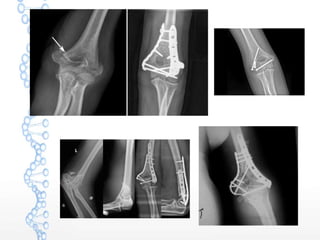

Operative treatment

 Indications

 Displaced fractures

 Comminuted fractures in young patient

 Methods available

 Interfragmentary screws

 Dual plate fixation

 Total elbow arthroplasty